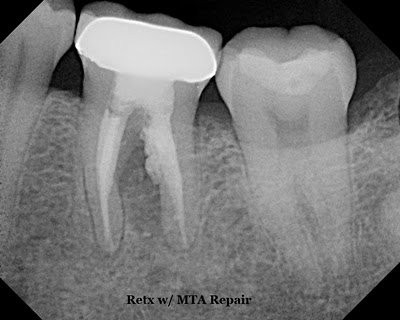

#19 was retreated and resorptive defect repaired with MTA. You can see the resorptive defect was opened more aggressively and there was extrusion of MTA into the periodontal ligament.